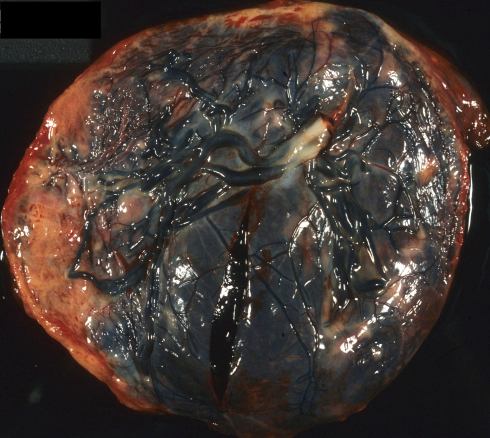

Fig 6a The fetal surface of this placenta demonstrates a raised tan margin that appeared to be a circumvallate placenta with a large Breus mole. The margin however was not typically folded in but appeared simply raised.

Fig 28a: The fetal surface of this placenta demonstrates a raised tan margin that appeared to be a circumvallate placenta with a large Breus mole. The margin however was not typically folded in but appeared simply raised.